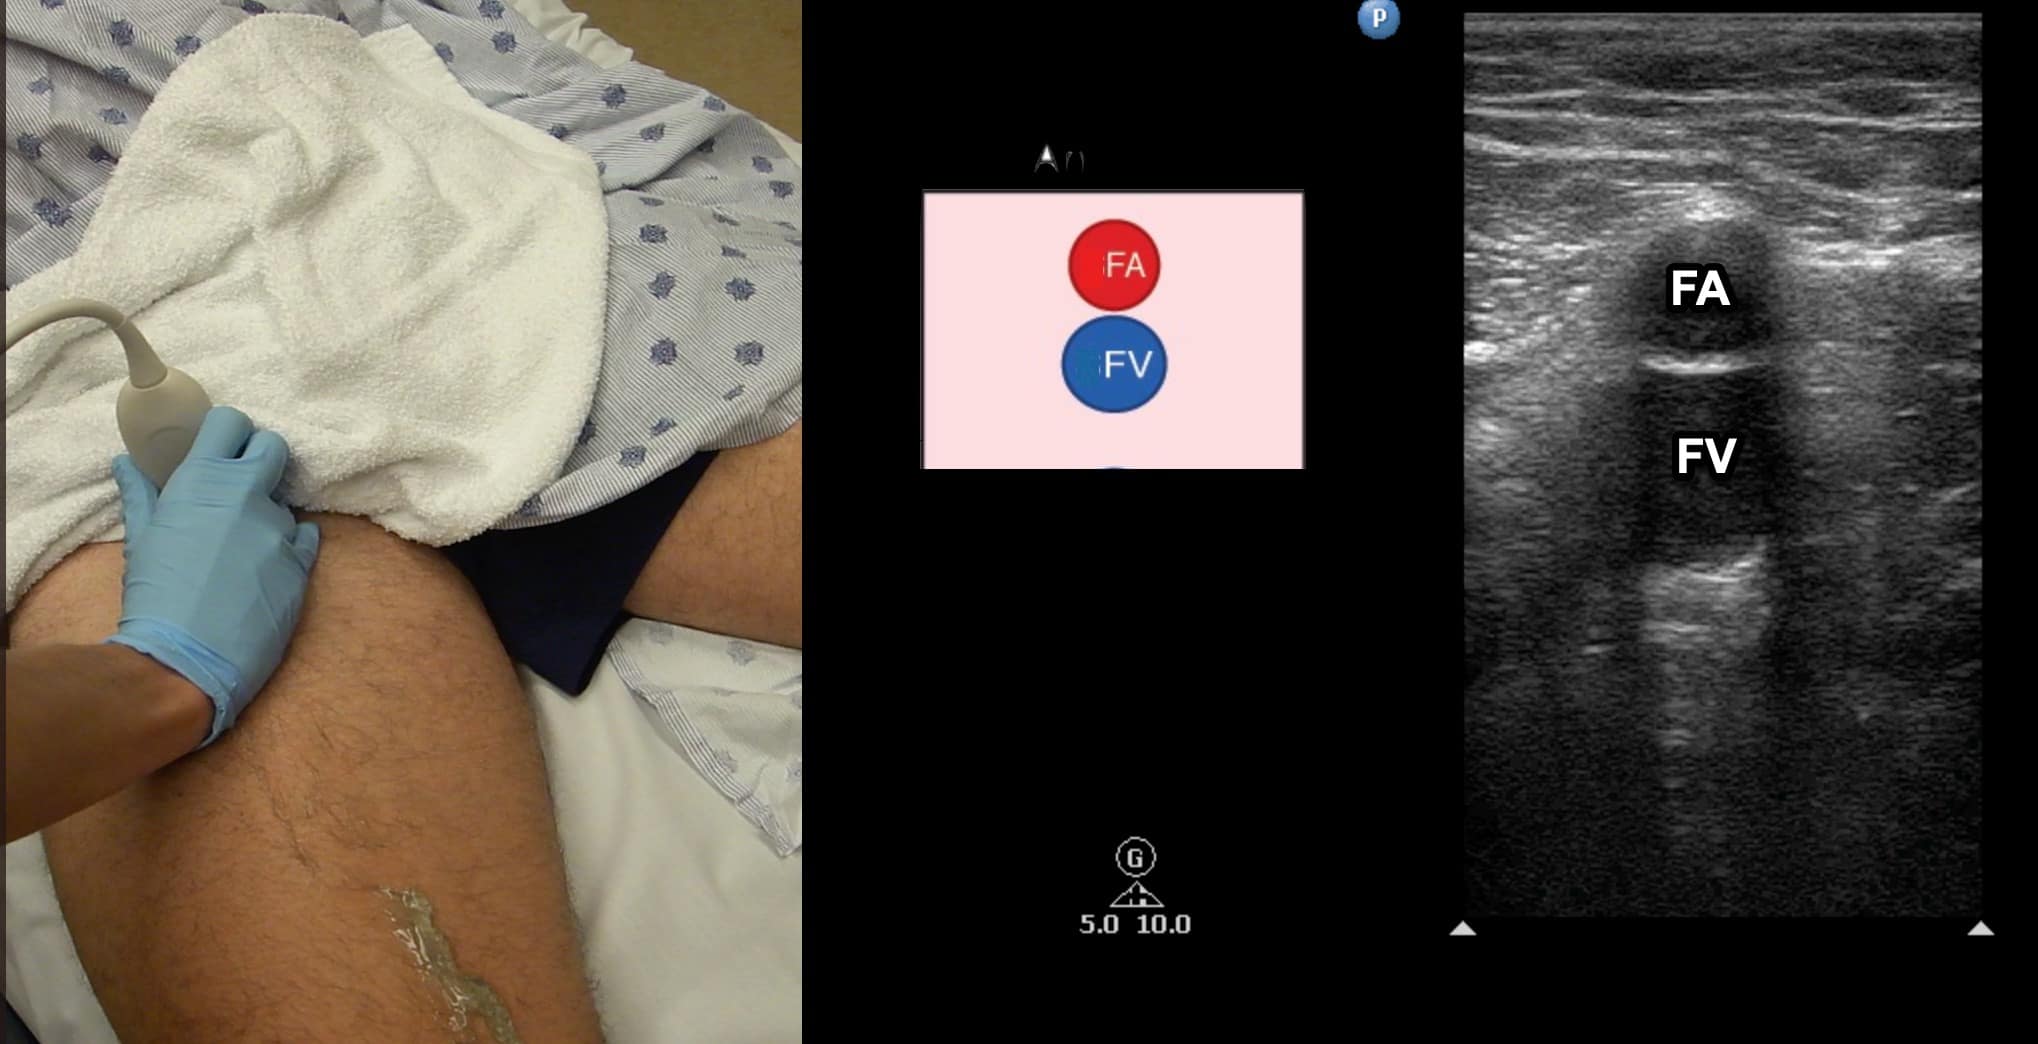

The transducer is directed in a caudal direction following the CFV with intermittent compressions performed at 1-2 cm intervals looking for lack of compressibility or evidence of intraluminal echogenicity. The common femoral artery (CFA) will be noted first to divide into the femoral artery (FA) and profunda femoral artery (PFA) (Figure 5). The CFV is followed until it divides into the FV and the PFV with intermittent compressions continued (Figure 6). The PFV is an unlikely location of isolated LE DVT and does not need to be followed.

Figure 6. Split screen demonstrating transverse window of femoral vein (FV) with femoral artery (FA) located anterior. Transducer position shown.

Once at the CFV/FV junction, it is important to look for evidence of venous duplication. Venous duplication occurs in a significant number of patients and is seen most commonly in the region of the FV and PV (Figure 7). Failure to identify venous duplication could lead to missing a DVT that occurs in only one of the systems. The FA is seen anterior to the FV in this region (Figure 8). As the FV approaches the adductor canal, an anterior approach utilizing an increased field of depth can also be used to better visualize the vein. Compression at this level is done by placing the freehand posteriorly and squeezing since transducer pressure will not result in venous compression with this approach (Figure 9).

Figure 8. Split screen demonstrating transverse window of the mid-femoral vein (FV). Note that the FV is located deep to the femoral artery (FA). The deep femoral artery (DFA) and deep femoral vein (DFV) can no longer be visualized.

Figure 9. Two-hand technique for compressing the distal femoral vein (FV) in the adductor canal. An anterior or medial scanning approach can be utilized. Note the freehand that will be compressing is placed on the posterior aspect of the leg.